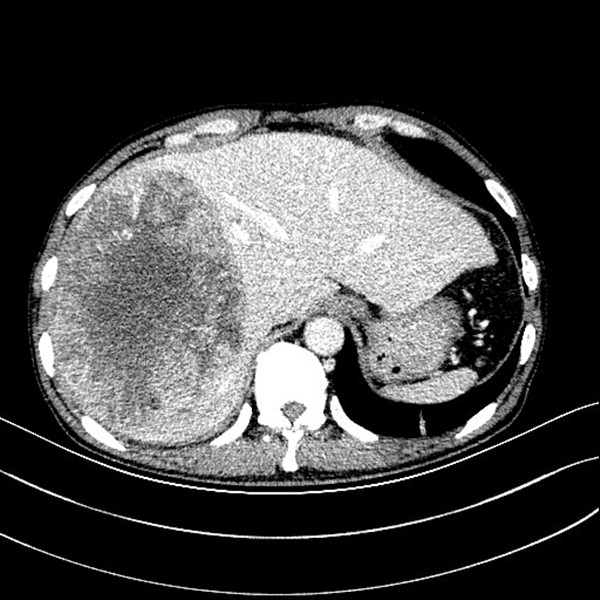

入院后积极完善相关检查,巨大的肿瘤几乎占据整个右半肝,同时伴有肝功异常,少量腹水,考虑肿瘤破裂出血可能。面对如此巨大的肿瘤,经我院肝癌MDT团队评估,认为:“患者门静脉主干和肝右静脉癌栓存在,肝癌射频治疗和介入治疗效果差,手术可能是延长患者生存期的唯一希望”。面对患者绝望而又无助的眼神,家人茫然痛苦的神情,陆宏伟教授及其团队思虑再三,患者存在门静脉右支和右肝静脉癌栓,系介入栓塞治疗禁忌症;巨大肝癌伴陈旧性出血,射频治疗已无意义;靶向药物索拉非尼治疗对一般农民家庭更是奢望;而外科手术切除是给患者延长生命的唯一希望,虽然手术难度巨大,但是一名外科医生不仅要有审时度势的胆识更要有知难而进的担当。

借助普外科3D辅助成像系统术前进行精准评估,实际肝体积3631ml,标准肝体积1288ml,肿瘤体积2048ml,左半肝体积(含尾状叶左半部分)1478ml,除右半肝剩余肝脏体积比标准肝体积大,说明患者左半肝已明显代偿,手术切除是可行的。术前肝功能Child-Pugh A级,ICG 15min滞留率 10.5%,无手术禁忌。